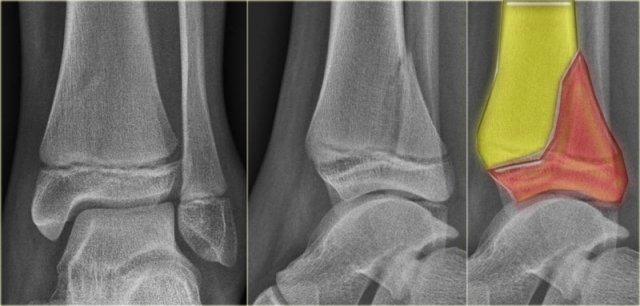

Hình X-quang cho thấy một gãy xương Tillaux kín đáo, được thể hiện rõ hơn trên các hình ảnh CT.

Hãy nghiên cứu kỹ các hình ảnh này và ghi nhớ các giai đoạn của chấn thương xoay ngoài.

Tổn thương ở đây là gì?

Đây là gãy xương Tillaux do bong điểm bám phần trước ngoài đầu dưới xương chày bởi khớp chêm trước.

Đây có thể là giai đoạn 2 của gãy xương Weber C.

Giai đoạn 1 là đứt dây chằng bên trong và giai đoạn 3 là gãy xương mác ở trên mức khớp chêm.

Vì vậy, chúng ta tiếp tục tìm kiếm giai đoạn 4, đó là đứt hoặc bong điểm bám của khớp chêm sau.

Bạn có nhìn thấy gãy xương tertius trên hình CT cắt ngang không?

Bệnh nhân này có chấn thương cổ chân không vững và cần được đặt vít khớp chêm.